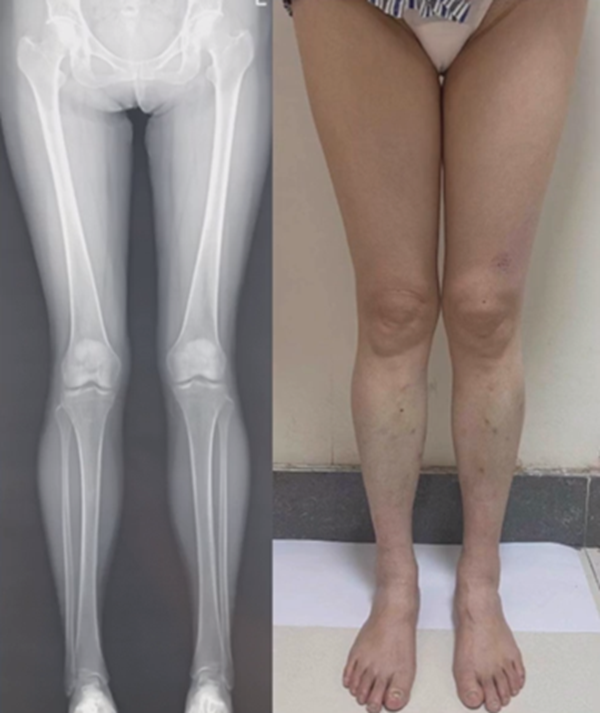

进行翻修,术前力线显示内翻。

术中发现螺钉松动,截骨端出现坎插迹象。

近端螺钉松开,调整力线,重新固定后,在外侧加小钢板抗旋

术后10周复查,力线较好。